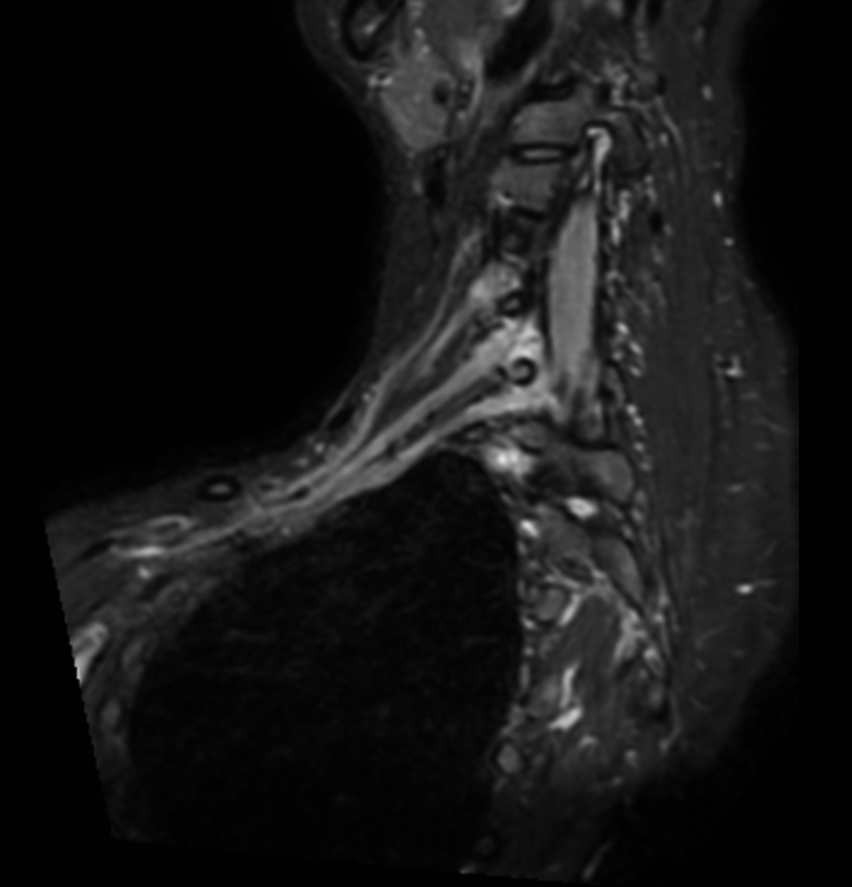

Coronal 3D STIR